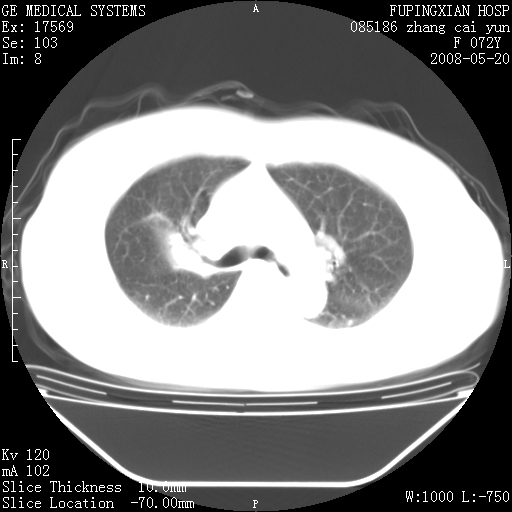

有节段性阻塞性肺炎与不张,近段支气管狭窄,周围散在肿大淋巴结影,以周围型肺癌可能性大,建议纤支镜检查。

建议纤支镜检查,考虑支气管内膜结核可能性大

右肺上叶实变影,内见支气管充气征,右上叶支气管通畅,肺门区未见软组织密度影,抗炎治疗有效,考虑炎症,建议继续抗炎治疗复查。

右肺阻塞性肺炎  不除外支气管内膜结核

考虑为:右肺上叶感染性病变。建议:1)继续抗炎治疗后复查。2)必要时行纤支镜检查。